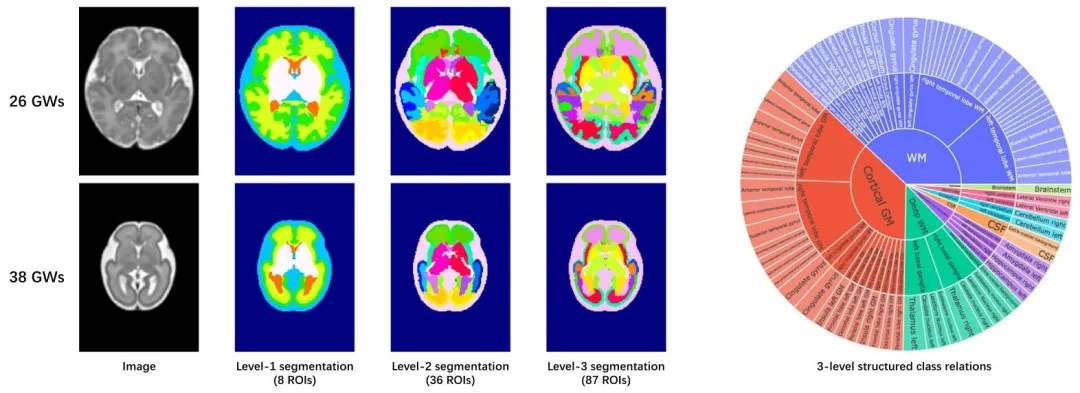

磁共振(MR)成像已成为评估胎儿脑发育与生长的重要工具,其提供的独特见解是产前超声无法企及的(Rutherford 等,2008)。基于磁共振图像的胎儿脑区分区技术,能够详细表征脑部解剖结构的变化,在研究胎儿脑发育规律及个体生长模式方面发挥着关键作用(Xu 等,2022)。此外,该技术还为监测和评估胎儿发育全过程中的脑结构提供了重要信息,助力神经发育障碍的早期检测与干预(Prayer,2005)。 传统胎儿脑区分区依赖人工标注,但这种方式不仅耗时费力,还严重依赖专家的专业经验,可能导致标注偏差。尤其是在处理大规模数据集时,人工标注的局限性更为突出——而大规模数据集对于全面的神经科学研究至关重要。因此,迫切需要一种稳健、准确的自动化方法,能够将胎儿脑磁共振图像分割为细粒度的解剖区域。然而,胎儿脑磁共振图像的自动分区面临诸多挑战:首先,与婴儿和成人图像相比,胎儿脑磁共振图像的组织对比度较低,增加了脑结构区分的难度;其次,妊娠期胎儿脑部形态会发生快速且显著的变化;再者,胎儿的不规则运动、低信噪比以及部分容积效应进一步降低了图像质量,从而限制了分割的准确性。 为应对这些挑战,研究人员已提出多种方法。传统的胎儿脑磁共振图像自动分区方法(Makropoulos 等,2014;Sm 等,2020;Machado-Rivas 等,2021;Vasung 等,2022)通常采用基于单图谱/多图谱配准的标签传播策略,分割精度不尽如人意,且分割后往往需要人工修正。为提高分割精度,深度学习技术已被应用于胎儿脑区分区任务。近期的创新包括:针对部分标注数据设计标签集损失函数(Fidon 等,2021a)、采用分布稳健优化提升模型泛化能力(Fidon 等,2021b)、开发条件图谱(Li 等,2022b;Pei 等,2021)。此外,胎儿组织标注(FeTA)挑战赛(Payette 等,2020、2022、2023、2024)也证明了深度学习方法在实现更准确、稳健的胎儿脑分割方面的巨大潜力。然而,现有方法均忽略了脑解剖结构在不同层级(即 8 个、36 个和 87 个感兴趣区域)的层级特征(见图 1)。这 87 个脑区是根据发育中人类连接组计划(dHCP)的模板定义的(Makropoulos 等,2018、2014)。这种层级特征对提高分割精度至关重要,原因在于:(1)直接将胎儿脑部分割为 87 个区域是一项极具挑战性的任务;(2)层级标签能够提供互补信息,可相互提升分割性能。此外,胎儿脑区分区还面临高质量真实分割标签稀缺、不同磁共振扫描仪及成像协议导致图像变异等问题。 为此,我们提出一种基于深度学习的新型模型——HPNet,用于胎儿脑区的分层分区。如图 1 所示,该模型构建了一种树状层级结构,实现从粗到细的多级别分割。这种分层设计明确编码了脑区之间从一般到具体的关系,使模型能够有效将全脑分割为 87 个细粒度脑区。具体而言,初始层级网络专注于分割 8 个粗粒度脑区;随后,第二层级网络对这 8 个脑区进行细化,分割为 36 个相对精细的脑区;最终,第三层级网络进一步细化至 87 个细粒度脑区。在此过程中,基础层级(即粗粒度)网络会将其特征传递给更高层级(即细粒度)网络。因此,涉及标签数量较少的粗粒度网络更易于训练,并能为细粒度网络提供有价值的辅助(Huang 等,2017)。此外,我们引入分层损失函数来建模层级间的关系,使细粒度分割任务能够借助粗粒度层级的引导,从而更高效地完成细粒度分割的训练。除分层结构外,模型还集成了基于分割标签的条件数据增强模块。该模块通过模拟组织外观和强度的变异,生成具有不同对比度、纹理和噪声水平的多样化训练图像。增强后的训练数据有效缓解了成像差异带来的挑战,使模型能够在多中心数据集上实现精准的胎儿脑分割。进一步地,我们将该数据增强模块融入半监督学习框架,以解决高质量标注数据稀缺的问题,并提升模型的泛化能力。大量实验表明,我们的模型不仅具有较强的泛化能力,还在胎儿脑磁共振图像分区任务中优于现有的最先进方法。 本研究在先前工作(Huang 等,2024)的基础上取得了以下关键进展:(1)优化了数据增强策略,生成了与真实数据分布一致的合成数据,并通过系统实验进行了验证;(2)拓展了实验内容,进行了全面的方法对比和深入的结果分析;(3)完善了理论框架,新增了相关工作、局限性及未来方向等章节;(4)明确表征了分层分割标签之间的关系;(5)强化了半监督学习的集成,并对方法进行了更清晰的阐释。与先前版本相比,这些改进提升了框架的方法论水平和实际应用价值。 本文的其余部分结构如下:第 2 节综述胎儿脑区分区及半监督分割方法的相关研究;第 3 节详细介绍所提分层学习框架及数据增强策略;第 4 节提供数据集、实现细节及实验结果;最后,第 5 节进行讨论。

Fig. 1. Hierarchical segmentation labels for the fetal brain at 23 and 38 gestational weeks (GWs). The sunburst chart on the right illustrates the structuredrelationships between the three-level segmentation labels

图1 妊娠23周和38周胎儿脑部的分层分割标签。右侧的旭日图展示了三级分割标签之间的结构化关系。